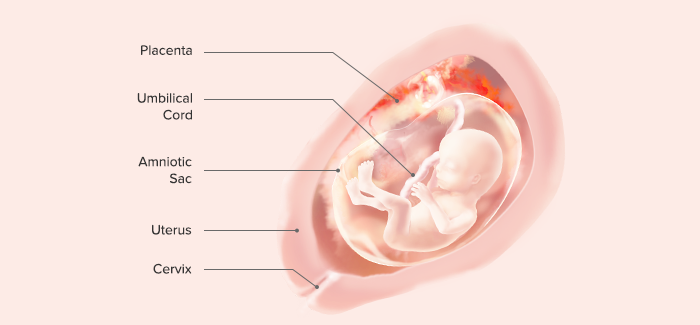

وضعیت جنین در هفته هفدهم بارداری

از هفته هفدهم باید مراقب حرفهایی که میزنید باشید زیرا جنینتان بهصورت کامل آنها را میشنود. پس بهتر است از این به بعد با فکر قبلی و با کلمات بهتری با او صحبت کنید و تا میتوانید از حرفهای مثبت و امیدوارکننده استفاده کنید. به دلیل بافتهای چربی که زیر پوست جنین وجود دارد این هفته کمی چاقتر به نظر میرسد. این بافتهای چربی نقش بسیار مهمی در تولید حرارت و سوختوساز بدن دارند.

حالا وزن کودک شما مجموع آب و چربی است و 89 گرم وزن کودک را آب و 5 گرم با چربی تشکیل داده است. اکنون مفصلهای دست جنین شما شکل گرفته و خیلی راحت میتواند دست و پای خود را تکان بدهد و هر چه زمان بیشتری میگذرد غضروفها سفتتر میشوند و به استخوان تبدیل میشوند.

بااینکه در این هفته هنوز چشمهای کودک شما بسته است اما مژه روی چشمهای او نمایان میشود. درصورتیکه جنین شما دختر باشد تکامل تخمکها اتفاق میافتد و درصورتیکه جنین شما پسر باشد تکامل اسپرمها اتفاق میافتد. قبل از تولد نوزاد دختر میلیونها تخمک در بدن او رشد میکنند و در جنین پسر هم در انتهای شکم رشد بیضهها شروع میشود و در آخر حاملگی بیضهها در کیسه بیضه جای میگیرند. حالا جنین شما 13 سانتیمتر قد و 140 گرم وزن دارد.

در هفته هفدهم شکم مادر بزرگتر از قبل شده و هرچه حاملگی پیشرفت میکند رحم دایرهای تر و گردتر میشود و شکلی شبیه تخممرغ میگیرد که چون رشد طولی رحم سریعتر است به این شکل درمیآید. در طول این مدت ضخامت جفت به 54.2 سانتیمتر میرسد و رحم در 5 سانتیمتری زیر ناف است. همین قضیه باعث میشود که به اجزای شکم فشار وارد شود تا به کنار بروند و جای کافی برای رحم وجود داشته باشد.